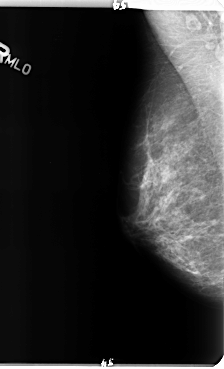

B_3150_1.RIGHT_MLO

RIGHT_CC LINES 4776 PIXELS_PER_LINE 2728 BITS_PER_PIXEL 12 RESOLUTION 50 NON_OVERLAY

RIGHT_MLO LINES 4792 PIXELS_PER_LINE 2912 BITS_PER_PIXEL 12 RESOLUTION 50 NON_OVERLAY